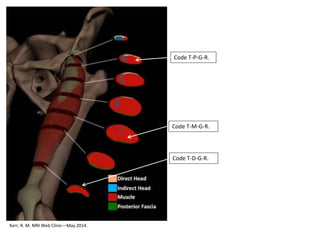

Examples Direct RF Injuries

Kerr, R. M. MRI Web Clinic—May 2014.

Code T-D-G-R.

Code T-P-G-R.

Code T-M-G-R.